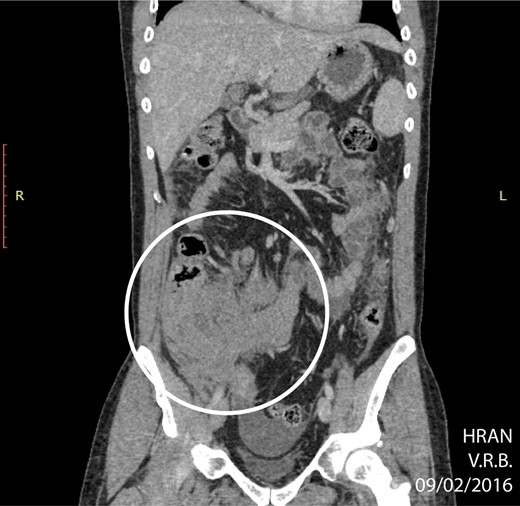

The surgery was indicated at the moment of clinical diagnosis, dismissing any imaging techniques. Even though CT-scanning is not mandatory, it grants over 90% sensitivity and specificity for acute appendicitis and helps with other differential diagnoses [6]. In this case, the CT-scan was only solicited after the lymphoma diagnosis, revealing a bulky and extensive mass in the right iliac fossa, poorly delimited, along with right pyeloureteral dilation. A probable diagnosis of appendiceal neoplasms can be made based on the increased diameter of the appendix shown on CT-scans (>3 cm), which is out of proportion for a non-tumoral appendicitis [5]. The specificity for lymphoma increases when abdominal lymphadenopathy or aneurysmal dilation of the appendiceal lumen are present [7]. These findings corroborate with a pre-operative suspicion of a primary appendiceal neoplasm.

CT of abdomen (coronal plane) highlighting an extensive, ill-defined mass localized in the right iliac fossa (circle) (02/09/16).